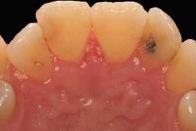

Occasionally, people develop “bumps” on the gums or other discolorations due to trauma, irritations, hormonal imbalances during pregnancy, or with the use of smokeless tobacco. In many instances, these changes are nothing to worry about, but they should be evaluated by a dental professional just to be safe. Certain oral lesions can be cancerous and are best treated in their early stages.

To evaluate these bumps and lesions, Dr. Caldwell or Dr. Dimmitt will perform a procedure known as a biopsy. Depending on the size of the lesion, it will either be removed completely or a small piece will be sampled for further evaluation. The tissue sample is sent to a laboratory for examination under a microscope by a highly trained Oral Pathologist. Our doctors then work with the Oral Pathologist to determine a diagnosis for the lesion. The entire process usually takes a few weeks from the time of biopsy to final diagnosis.